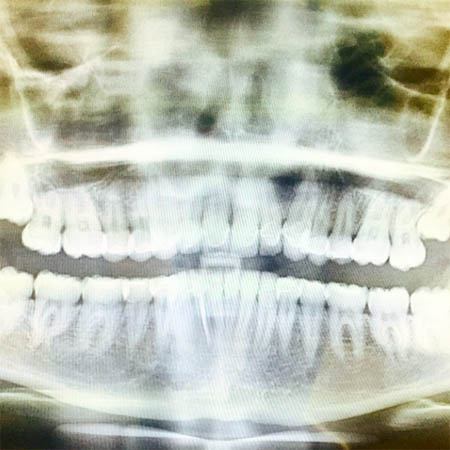

2日前に歯のレントゲン写真をアップしたマイリーは、先日、抜いた歯5本、両頬を冷やしている様子などの写真を公開し、「助けて。くそやばい」とコメント。

▲レントゲン写真を公開。